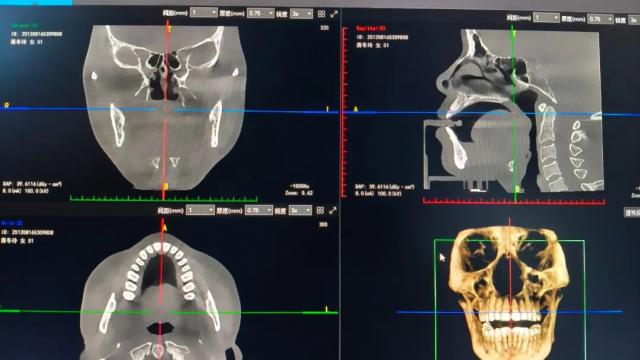

此次引进的口腔CBCT设备,被誉为口腔诊疗的“三维导航”,相较于传统影像检查具有显著优势。

通过三维重建技术,医生能直观掌握下颌神经管走向、上颌窦与牙根关系等关键解剖信息,有效避免治疗中的“盲操作”,大幅降低手术风险,为制定个性化诊疗方案提供科学依据。